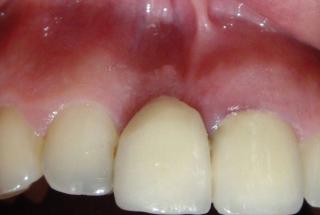

Clinical cases

MPI closely monitors clinical cases in the market to ensure their correct functioning and successful outcome.